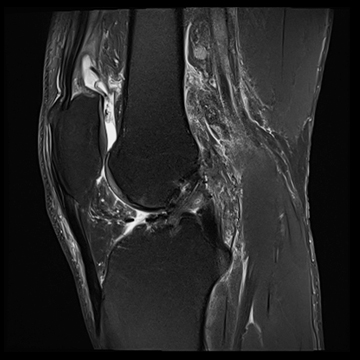

膝関節

PD 脂肪抑制

T1 TSE

3D TrueFISP脂肪抑制